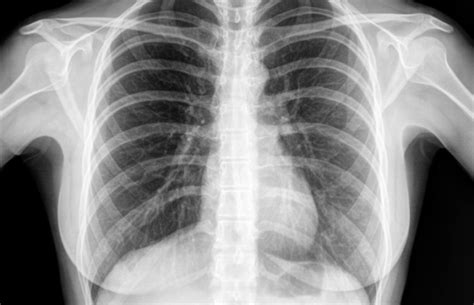

2. Lung Fields and Parenchyma

The lung fields should appear clear and dark on a normal chest X-ray, indicating the absence of consolidation or other pathologies. The lung parenchyma, which includes the alveoli, bronchioles, and capillaries, should not show any signs of disease such as opacities, nodules, or cavitations. The presence of any abnormalities in the lung fields can suggest a wide range of conditions, from infections to chronic diseases like emphysema. Thus, a thorough examination of the lung fields is essential for determining the normalcy of a chest X-ray.